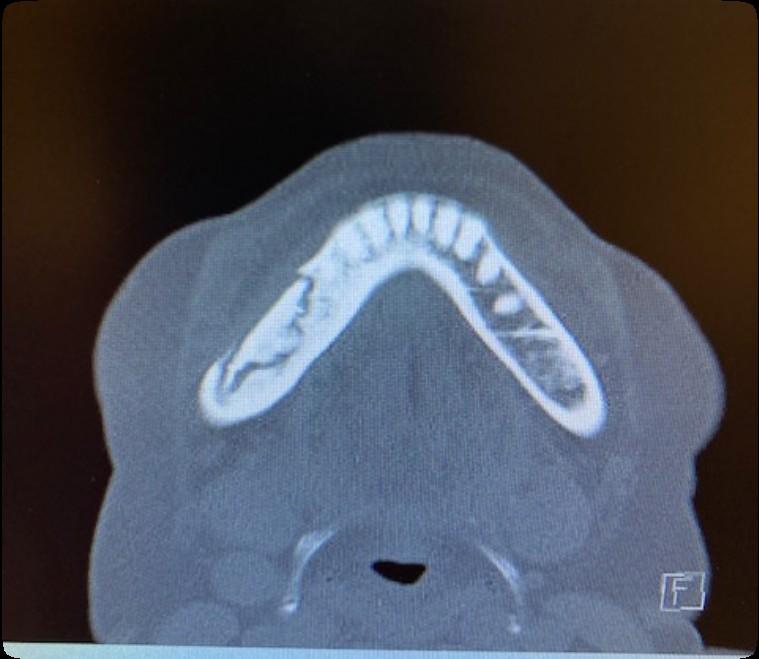

Osteonecrosis of the Jaw

MRONJ: Medication Related Osteonecrosis of the Jaw

• Rare oral side effect called osteonecrosis of the jaw that is associated with certain medications, bone-modifying agents.

• Osteonecrosis of the jaw is a condition where small area(s) of the jawbone have difficulty healing and the bone starts to breakdown and die.

Bone Modifying Agents

• Medications used to prevent bone loss and demineralization (weakening/destruction)

• Some are given as pills; others must be given through an IV

• Examples of these medications include Actonel™, Zometa™, Fosamax™, and Boniva™, Xgeva™, and Prolia™

How Common is MRONJ?

The risk is thought to be less than 1% for patients taking IV bonemodifying agents, and at least ten times less likely than that for patients taking the drugs by mouth.

If I take these medications, am I automatically at risk?

• Anyone who takes these medications has a chance of developing ONJ.

• However, most reported cases occur after a type of oral “injury” – which could a tooth extraction, chronic periodontal (gum) disease, an oral surgical procedure, or simply a nonhealing traumatic ulceration.

• Tobacco use, treatment with corticosteroids, long-term use of bonemodifying agents, and diabetes also may increase the risk of this condition occurring.

What are the signs of MRONJ?

• The hallmarks of ONJ are exposed bone or gum/mucosa/tissue wounds that heal very slowly or do not heal at all for eight weeks or more after an injury to the mouth.

• Some patients report that this begins with a feeling of “roughness” on the gum tissue. If these open wounds become infected, there may be pus or swelling in the adjacent gum tissue.

• Many times, this condition is painless in the beginning, and patients only experience pain after the exposed bone becomes infected.

How is MRONJ treated?

• Education

• Careful oral hygiene

• Conservative interventions

• Avoid surgical intervention, if possible

• PATIENCE!